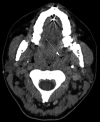

Lemierre's syndrome is a condition characterized by septicemia, with bacteremia, thrombophlebitis of the internal jugular vein (IJV), and septic embolization to distant organs following a recent upper respiratory infection (URI). Fusobacterium necrophorum, an anaerobic Gram-negative rod, has been mostly implicated as the causative organism of this condition that tends to affect healthy teenagers and young adults. While once regarded as a disease of old, it has seen a resurgence in recent times, possibly due to antibiotic stewardship and current trends of reduced antibiotic use for URIs. It is important that the modern physician has a high index of suspicion, as well as the characteristic presentation of this potentially fatal illness. Current treatment guidelines are centered on the use of appropriate antibiotics, drainage of purulent collections when possible, and, in some situations, anticoagulants have been utilized. This study describes a case of a young lady who presented with symptoms of chest pain and deteriorating oxygen saturations following recent treatment for acute tonsillitis.